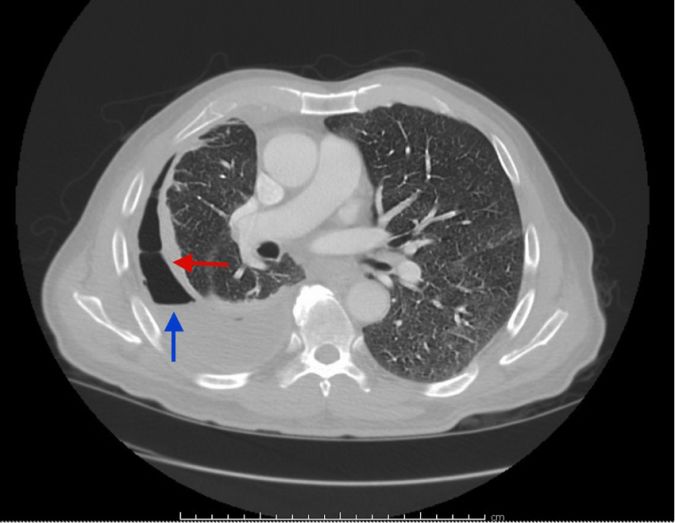

Hầu hết các phương pháp chụp chiếu sẽ giúp chẩn đoán MPE, lượng dịch màng phổi ít nhất 50ml là có thể phát hiện trên phim xquang phổi nghiêng và 200ml dịch là có thể thấy trên phim xquang phổi thẳng. Siêu âm màng phổi qua thành ngực nhạy hơn để phát hiện dịch và di căn màng phổi với dấu hiệu dày màng phổi, các dấu hiệu khác như vách hóa hay dịch khu trú.

Sự có mặt của các nốt màng phổi và các yếu tố khác như nốt cơ hoành hoặc dày màng phổi giúp dự báo ác tính từ 83-100%. Siêu âm màng phổi còn giúp điều trị với xác định vị trí chọc dịch và đặt dẫn lưu. Sau khi chọc hút, siêu âm còn giúp đánh giá khả năng giãn nở của phổi và tình trạng tràn khí màng phổi. Chụp CT ngực rất chính xác phát hiện MPE, đánh giá các thông tin về phổi, màng phổi dày>1cm, nốt màng phổi, dịch khu trú và các dấu hiệu ác tính khác.